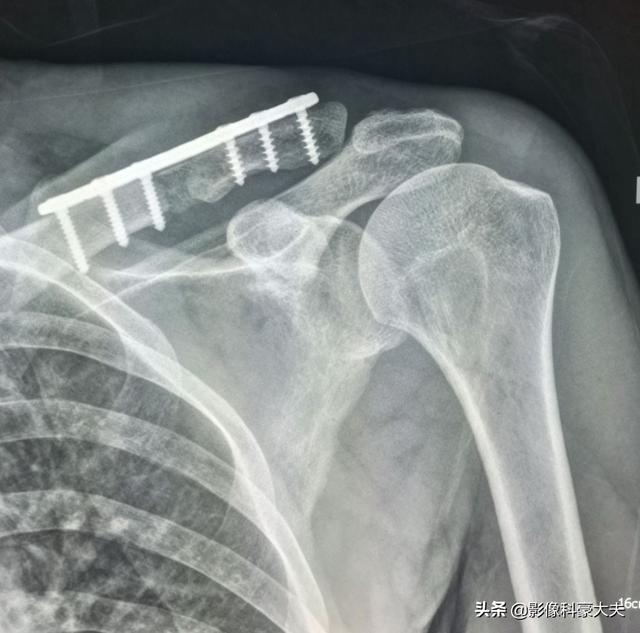

Es handelt sich um einen 58-jährigen schwulen Mann, der bei einer leichten Streckung seiner Schulter anhaltende Schmerzen verspürte und bei Röntgenaufnahmen hypodense Herde feststellte:

Es handelte sich um eine pathologische Fraktur, die durch geringe äußere Kräfte auf der Grundlage einer Knochenmetastase verursacht wurde. Es wurde eine Punktion durchgeführt und die Pathologie war eine Knochenmetastase eines schlecht differenzierten Lungenadenokarzinoms.

Dies ist die Operation zur internen Fixierung eines Schlüsselbeinbruchs, eines pathologischen Bruchs, der ohne chirurgischen Eingriff nur sehr schwer von selbst heilt.

Da normales Knochengewebe zerstört und durch Tumorgewebe ersetzt wird und sich die Tumorzellen ständig vermehren, sind an vielen Stellen mit Knochenmetastasen Weichteilschatten zu sehen, die bei oberflächlicher Lage auch ertastet werden können. Darüber hinaus führt die Erosion des normalen Knochengewebes durch das Tumorgewebe auch zur Zerstörung und Schwächung der normalen Knochenstruktur, so dass es unter normalen äußeren Kräften zu Brüchen kommen kann, die als pathologische Frakturen bezeichnet werden (siehe Abbildung unten). Neben Schmerzen und pathologischen Frakturen kann es bei Metastasen in der Wirbelsäule auch zu einer Kompression von Spinalnervenwurzeln mit Symptomen wie Empfindungsstörungen, Muskelschwäche und in einigen Fällen zu einer Hyperkalzämie kommen.